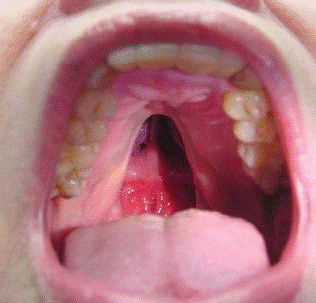

. Волчья пасть

Врождённый порок развития, заключающийся в

незаращении верхней челюсти и твёрдого нёба, в результате чего получается

расщелина, соединяющая полости рта и носа. Встречается приблизительно у 1 из

1000 новорождённых. Причиной является задержка срастания верхнечелюстных

отростков с сошником.

Различают четыре формы:

незаращение мягкого нёба;

незаращение мягкого и части твёрдого нёба;

полное одностороннее незаращение мягкого и

твёрдого нёба;

полное двустороннее незаращение.

Варианты незаращения твердого и мягкого неба:

а - незаращение язычка, короткое мягкое небо,

скрытый костный дефект; б - незаращение мягкого неба; в - незаращение мягкого и

частично твердого неба; г, д - полное незаращение (одностороннее и

двустороннее)